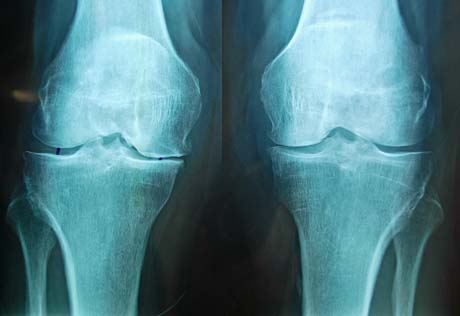

Ακτινολογική προεγχειρητική εικόνα των γονάτων άμφω. Βαριά εκφυλιστική οστεοαρθρίτιδα και στα δυο γόνατα.